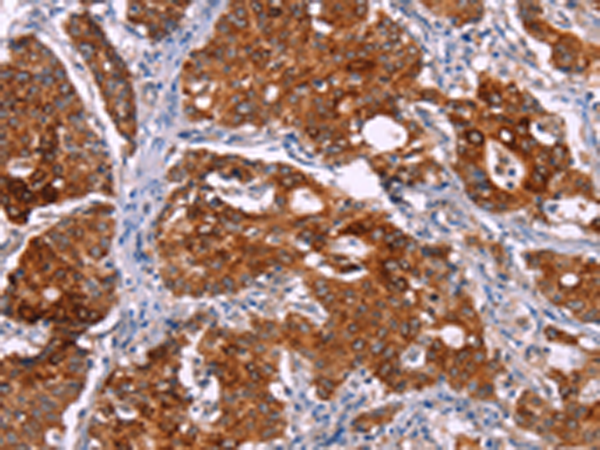

分类: 科研抗体货号: P11267别名: MG1; MUC5; MUC9; MUC-5B应用: WB,IHC反应种属: Human